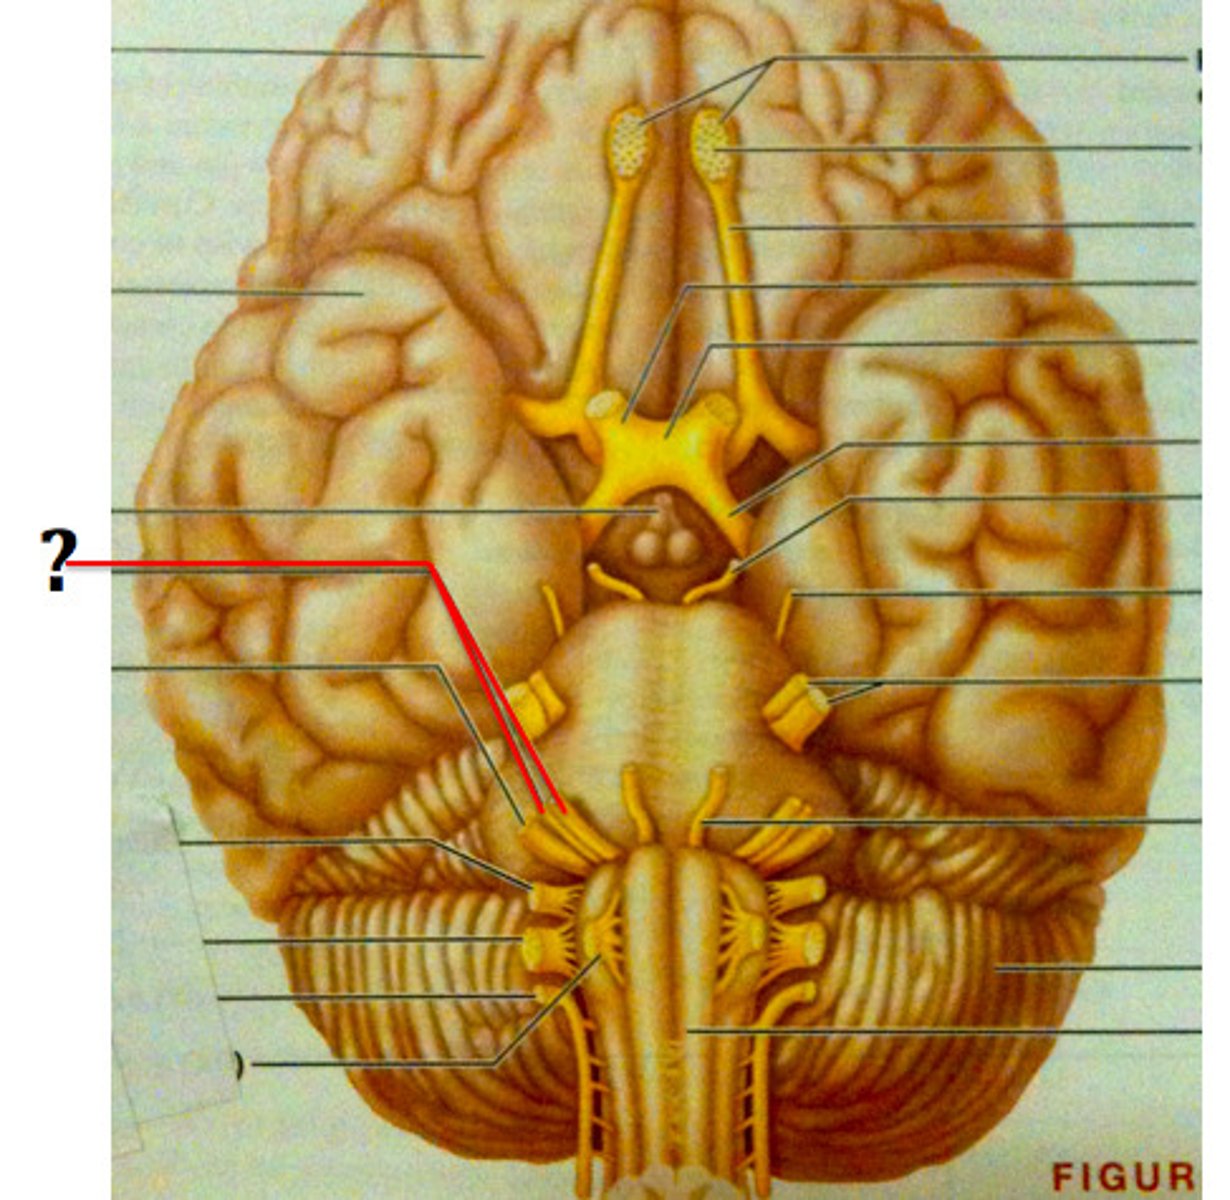

cranial nerves

12 pairs of nerves that carry messages to and from the brain

pons

center structure of the brain stem, located between the midbrain and the medulla oblongata

midbrain

or mesencephalon extends from pons to diencephalon. the pons is the center structure of the brain stem, located between the midbrain and the medulla oblongata